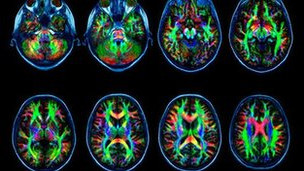

La adicción a internet cambia el cerebro

Las personas adictas a internet muestran cambios en el cerebro similares a los adictos a sustancias como drogas o alcohol, afirman investigadores en China. El estudio llevó a cabo escáneres cerebrales en 17...